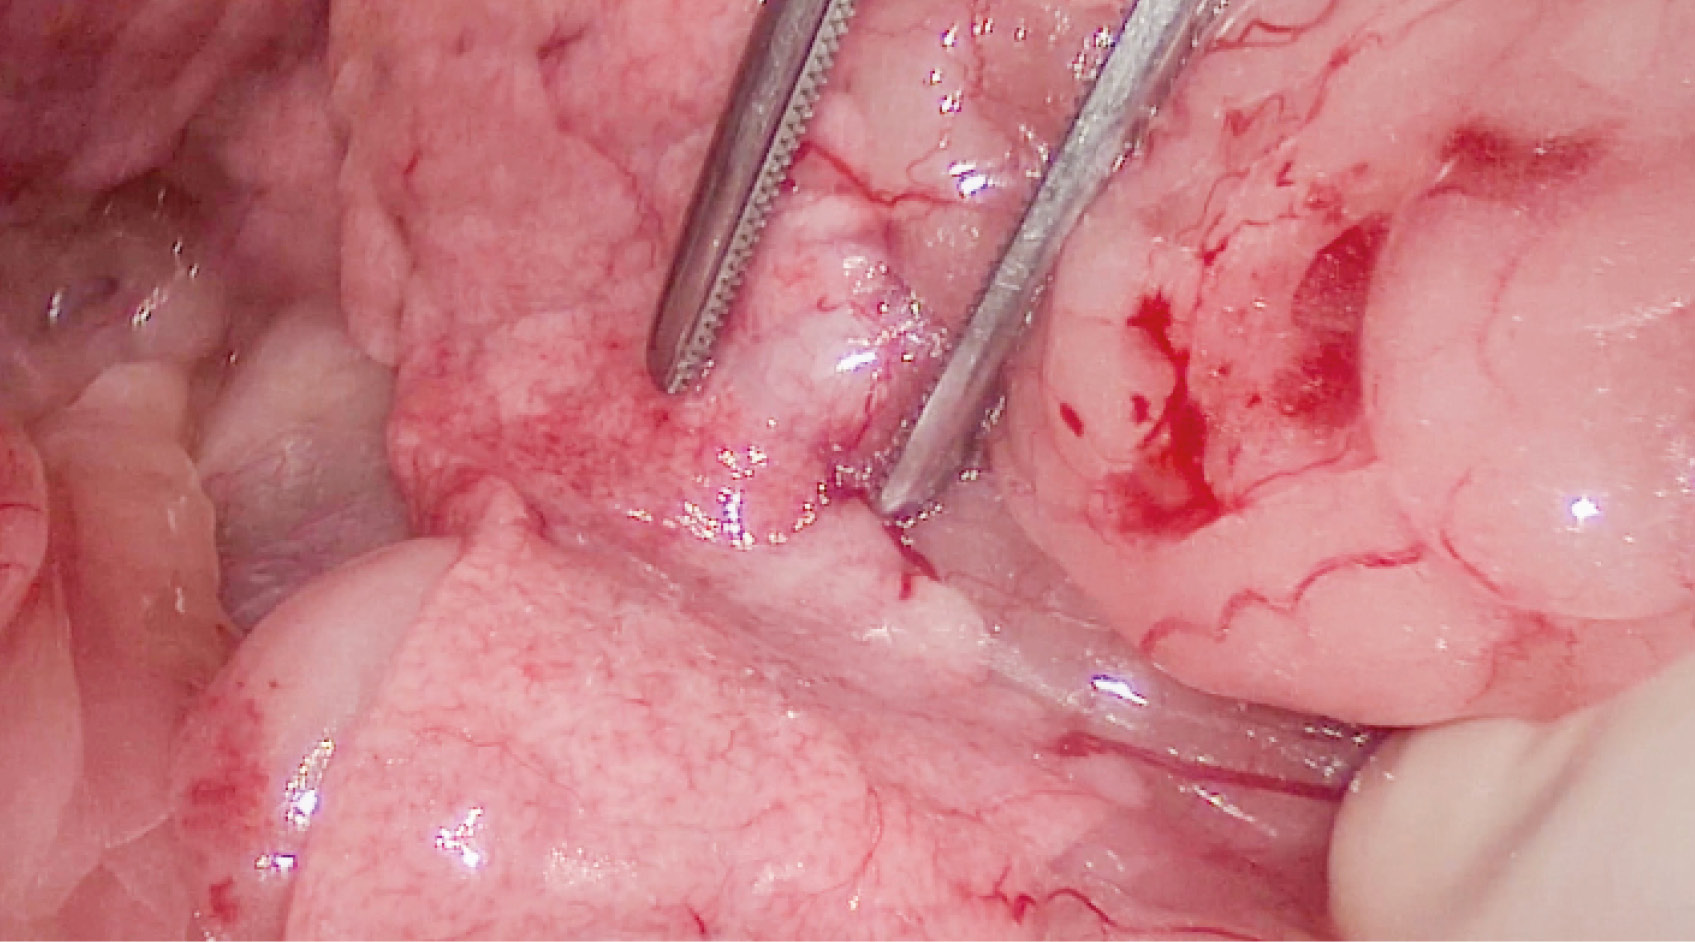

Se realizó la disección del lóbulo izquierdo y el cuerpo del páncreas, usando un sellador vascular/tisular, hasta una porción macroscópicamente libre de lesión. Se continuó con la disección de la vena porta y la vena gastroduodenal. A continuación, se colocaron tres torniquetes de Rummel (en la vena porta craneal y caudal a la invasión y en la vena gastroduodenal) y se procedió a realizar la venotomía de la vena porta y ligadura completa de la vena gastroduodenal al estar en la zona de la venotomía. De esta manera, se liberaron la porción del páncreas diseccionada y el trombo tumoral que invadía la vena porta. El cierre venoso se efectuó con sutura continua con polipropileno 6/0 USP y con hemoclips; después, se colocó un apósito de colágeno (vídeo 2).

Vídeo 2. Procedimiento quirúrgico completo. Pancreatectomía en bloque del lóbulo izquierdo, del cuerpo del páncreas y venotomía de la vena porta para retirar el trombo tumoral: disección del lóbulo izquierdo y cuerpo del páncreas con sellador vascular/tisular (y sección del páncreas en zona sana macroscópicamente), disección de la vena porta y la vena gastroduodenal, colocación de tres torniquetes de Rummel (en la vena porta craneal y caudal a la invasión y en la vena gastroduodenal), venotomía de la vena porta y ligadura completa de la vena gastroduodenal (ya que interfería con la zona de la venotomía), liberando así la porción del páncreas diseccionada y el trombo tumoral que invadía la vena porta. El cierre de la vena fue realizado con sutura continua con polipropileno 6/0 USP y con hemoclips, y después se colocó un apósito de colágeno.

Posteriormente, se realizó linfadenectomía pancreático-duodenal y la biopsia de dos lesiones hepáticas localizadas en el lóbulo lateral y medio derechos. Tras lavar el abdomen con solución salina estéril atemperada, se realizó el cierre de la cavidad abdominal de forma rutinaria en tres capas: muscular, subcutáneo y piel. Los tejidos extirpados fueron enviados al laboratorio para su estudio histopatológico (imagen 3).